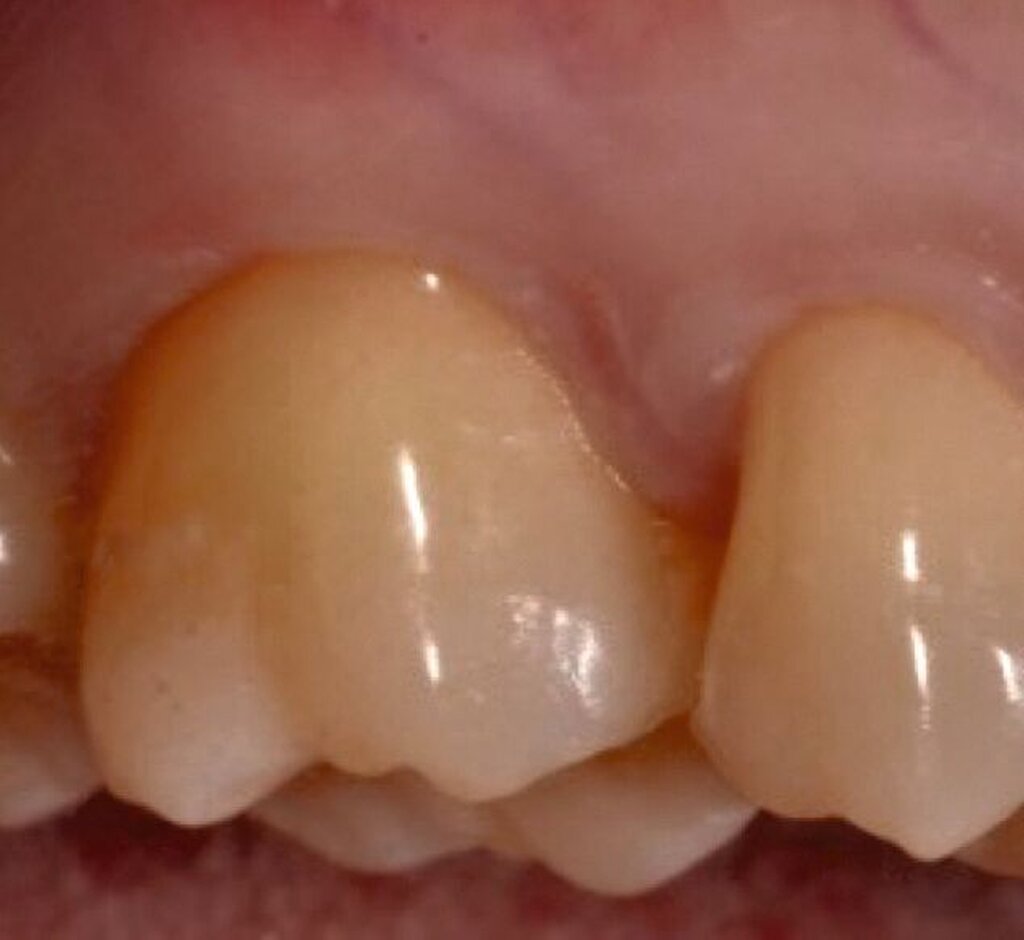

Fall 1 – einfach